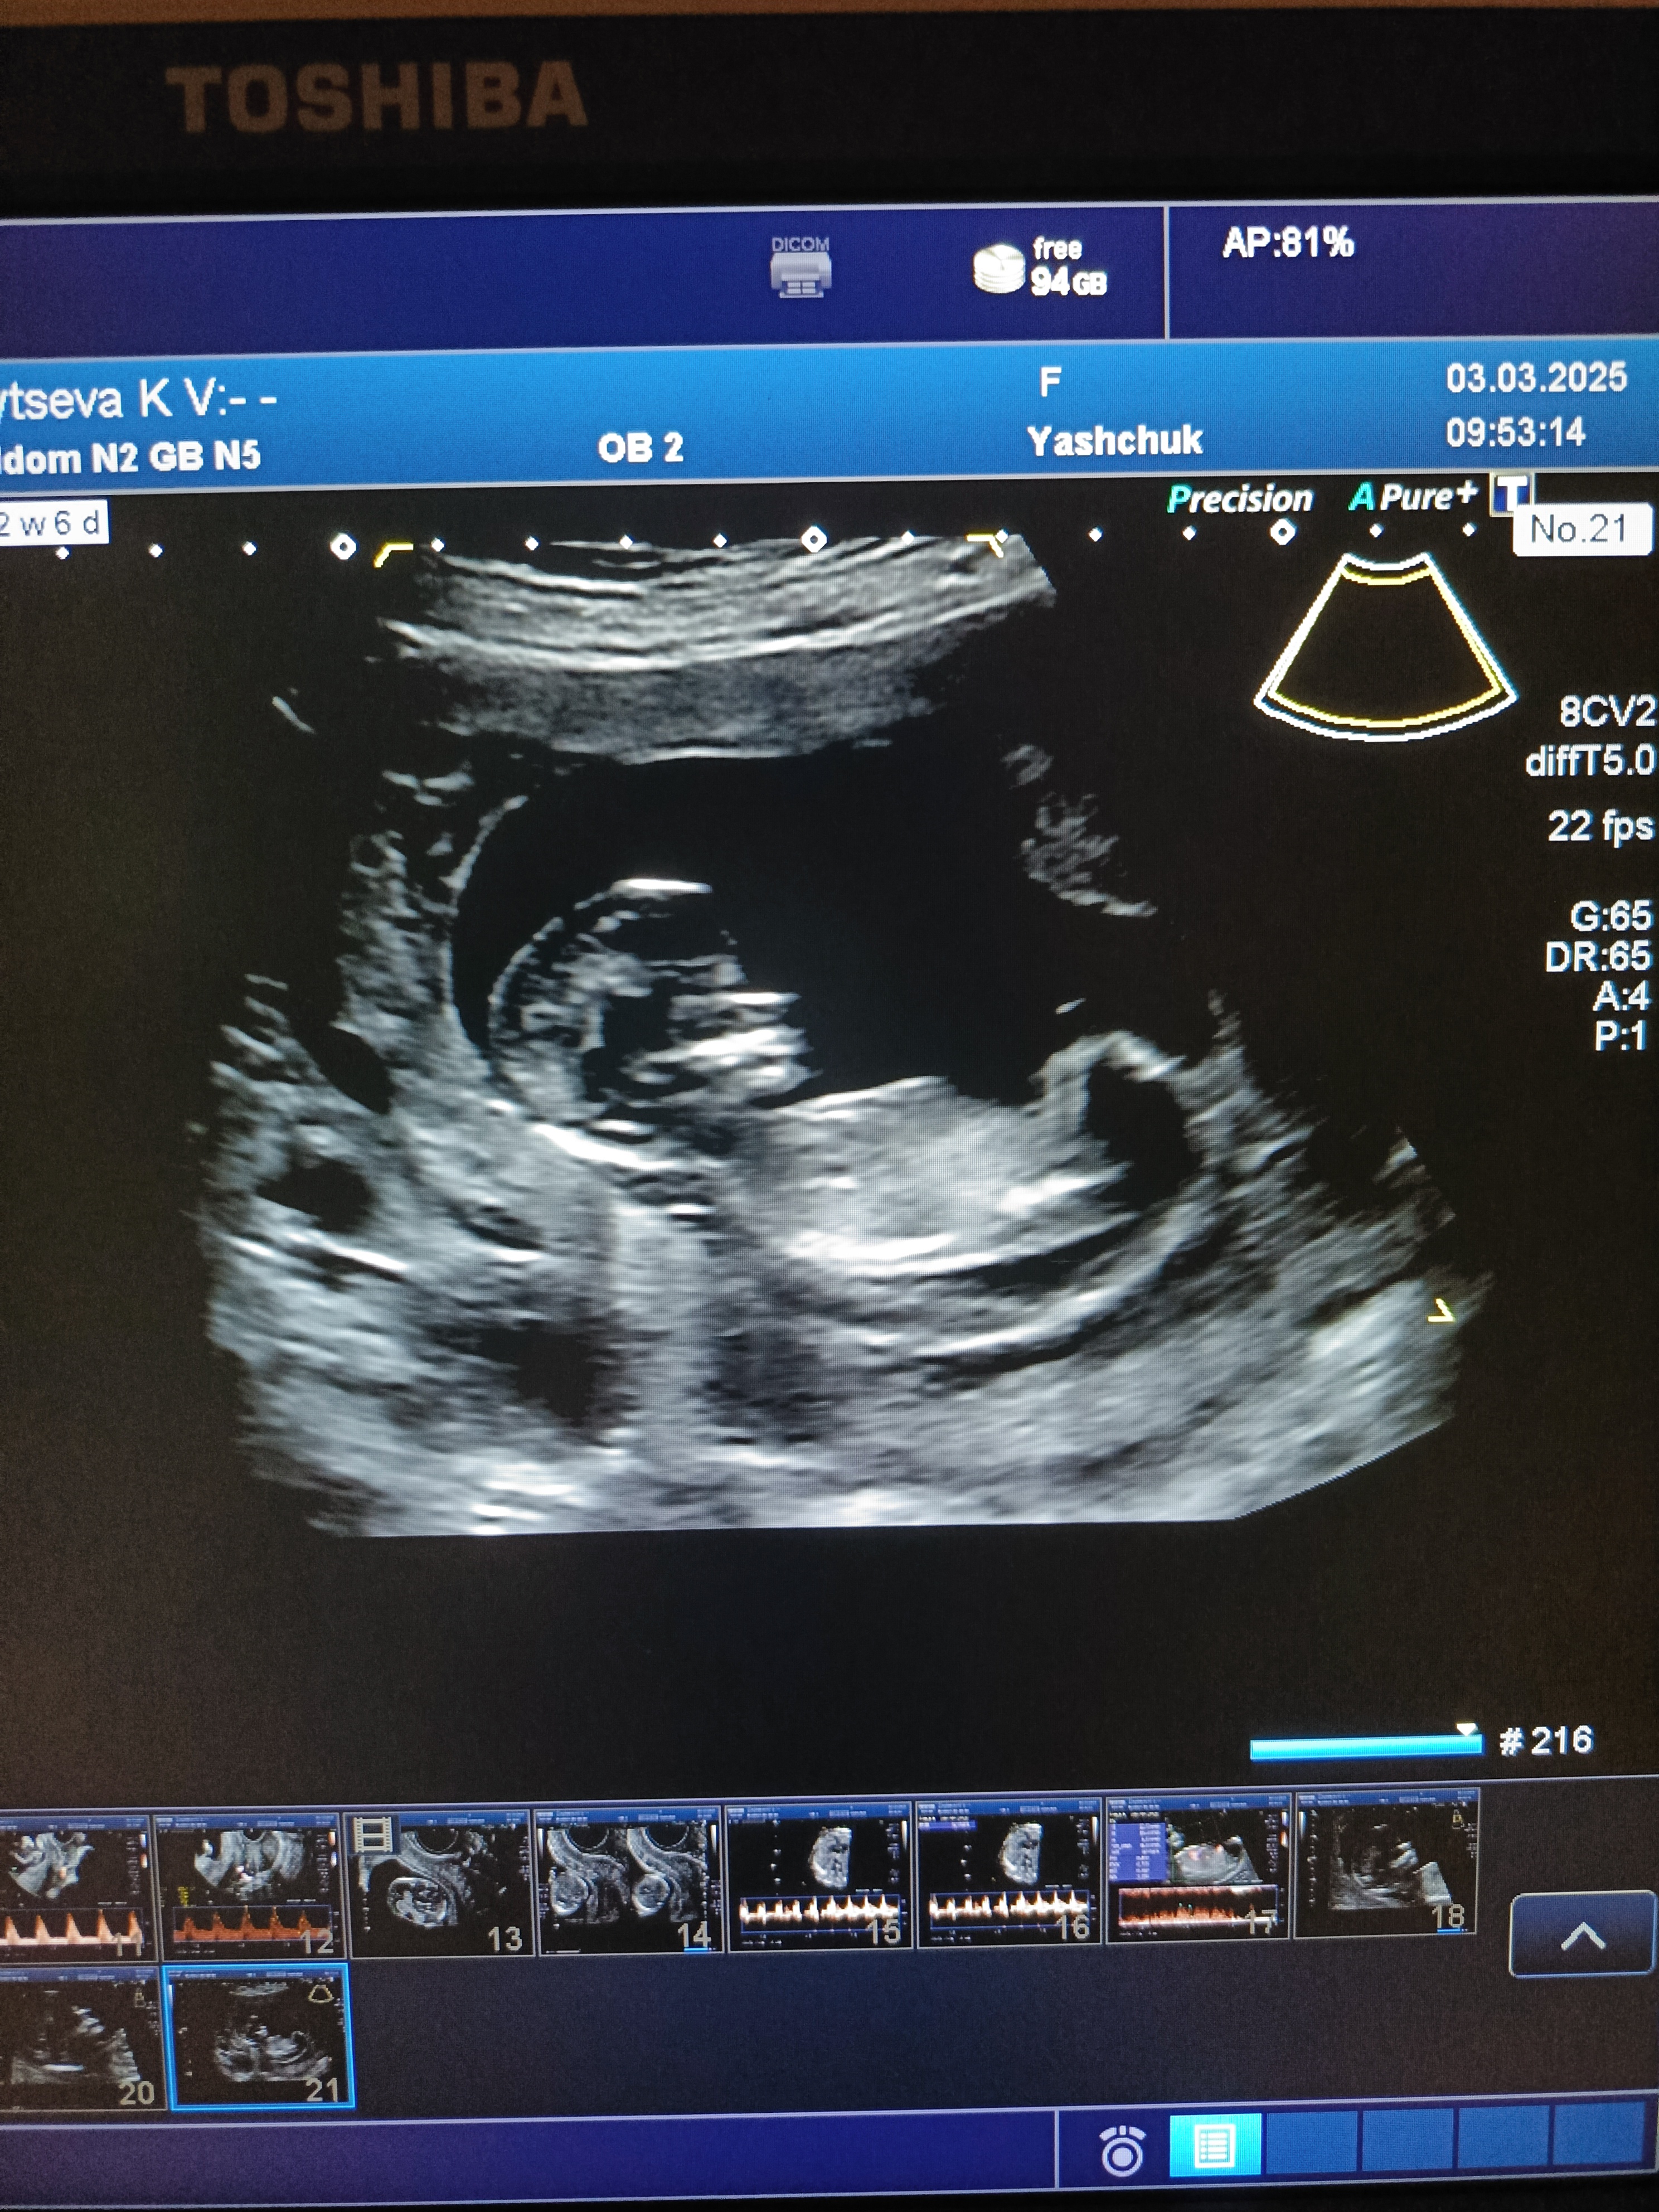

Первый скрининг пройден🫶 кто в домике живёт? 🫣

Анализы, скринингиДевочки, привет🫶 вчера прошёл наш первый первый скрининг, слава Богу, все хорошо и по узи и по крови🙏 малыш очень подвижный, не могли его датчиком поймать нормально)) фото поэтому размытое🙈 но вдруг кто-то разглядит хотя бы намёк, мальчишка или девочка? Буду очень благодарна🤗